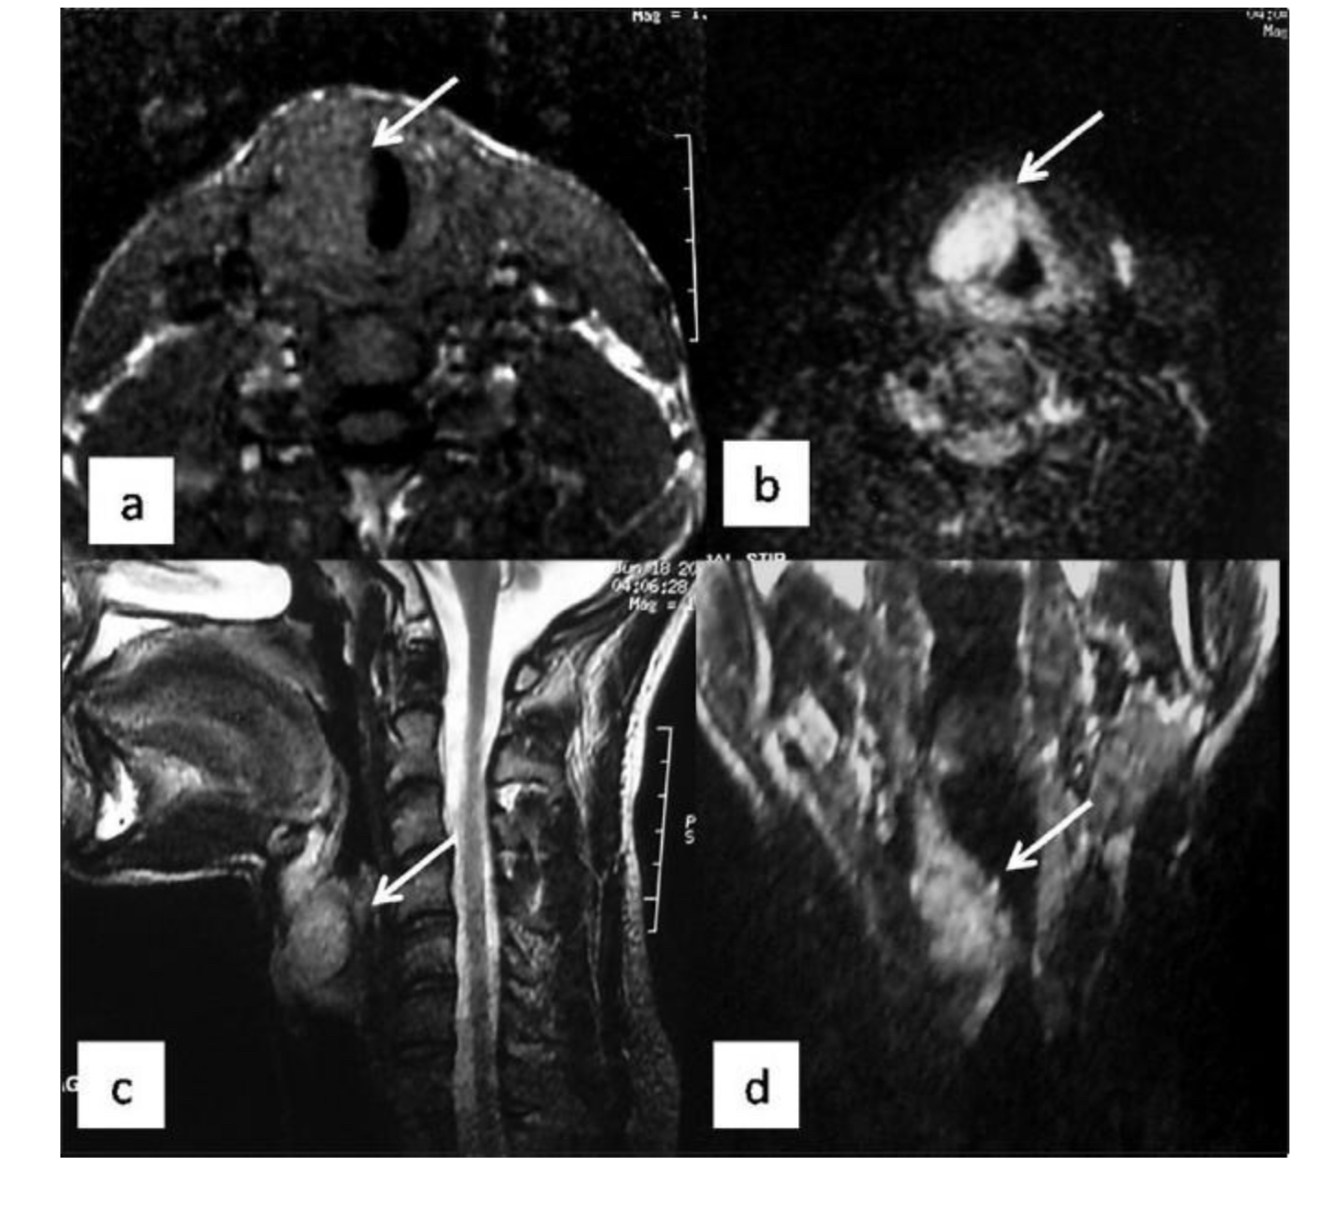

7

What pathology indicated?

A

Mass - right parotid gland

8

What does arrow indicate?

left parotid mass

9

What does arrow indicate ?

submandibular gland

10

Vocal cord Schwannoma